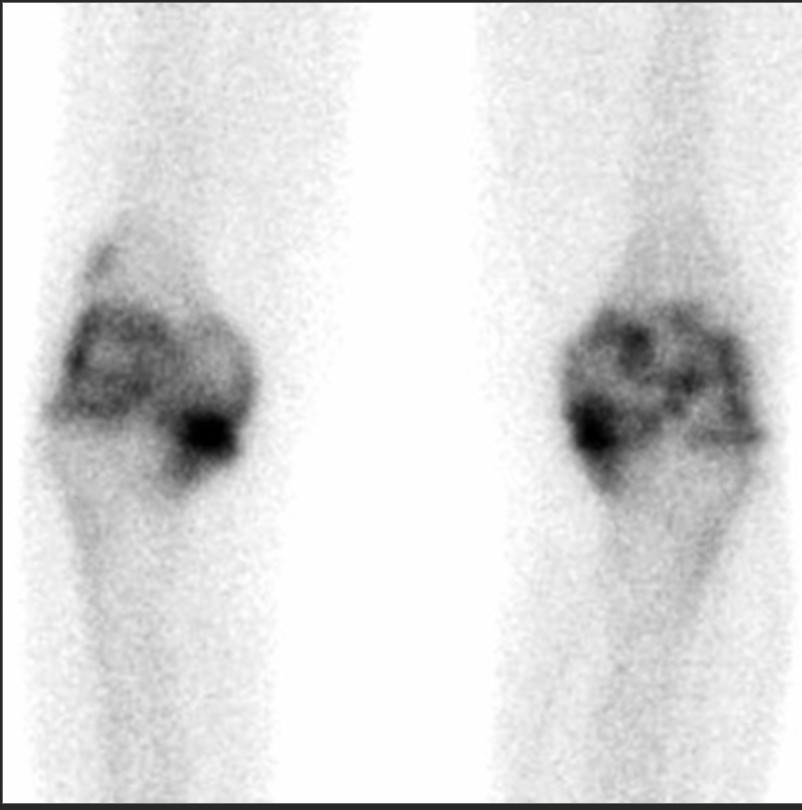

Osteoid Osteoma

• Focal area of uptake in lumbar spine of kid with scoliosis

• Double density sign ( basically centrally very hot and slightly less hot surrounding it)

• Pain better with NSAIDs, typically pain at night